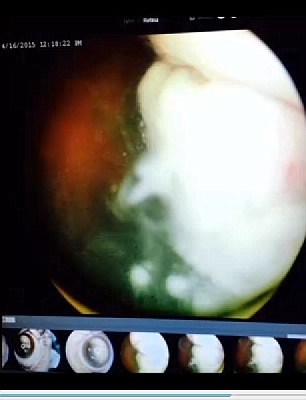

Το μάτι του μικρού Έιβερι ήταν κατά 75% καλυμμένο από όγκους. Διαγνώστηκε με ρετινοβλάστωμα, έναν σπάνιο όγκο της παιδικής ηλικίας που προσβάλει τον αμφιβληστροειδή. Ένα από τα συμπτώματα του όγκου, είναι το άσπρο χρώμα της κόρης του ματιού όταν το «χτυπάει» έντονο φως (λευκοκορία), σύμφωνα με τους οφθαλμιάτρους. Εξαιτίας την εξάπλωσης των όγκων στον αμφιβληστροειδή του άτυχου Έιβερι οι γιατροί αναγκάστηκαν να αφαιρέσουν το προσβεβλημένο απ’ τη νόσο μάτι. «Αν δεν το βγάζαμε, ο καρκίνος θα εξαπλωνόταν στο αίμα και τον εγκέφαλό του», εξηγεί η μαμά του.